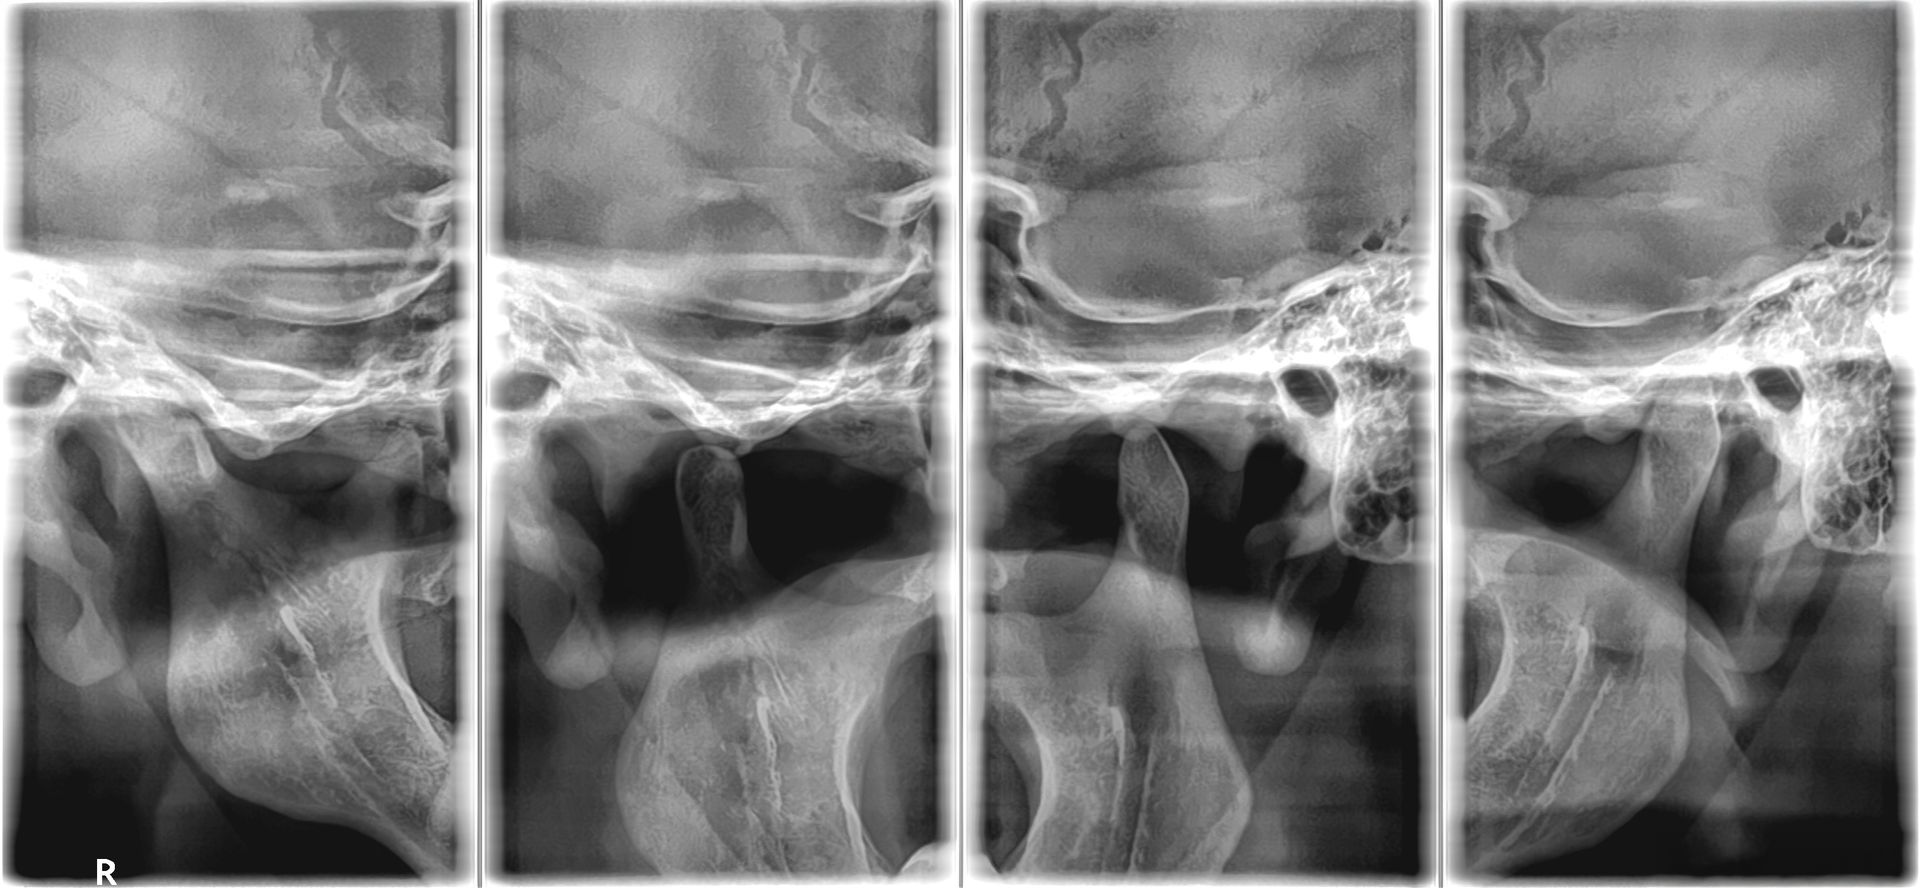

Uno de nuestros principales servicios es la adquisición de imágenes dentales 2D y 3D, fundamentales para un diagnóstico preciso y una planificación adecuada de tratamientos dentales.

Contamos con tecnología avanzada que nos permite obtener imágenes claras y detalladas de la boca y los tejidos circundantes, lo que es crucial para evaluar la salud dental y detectar posibles problemas.